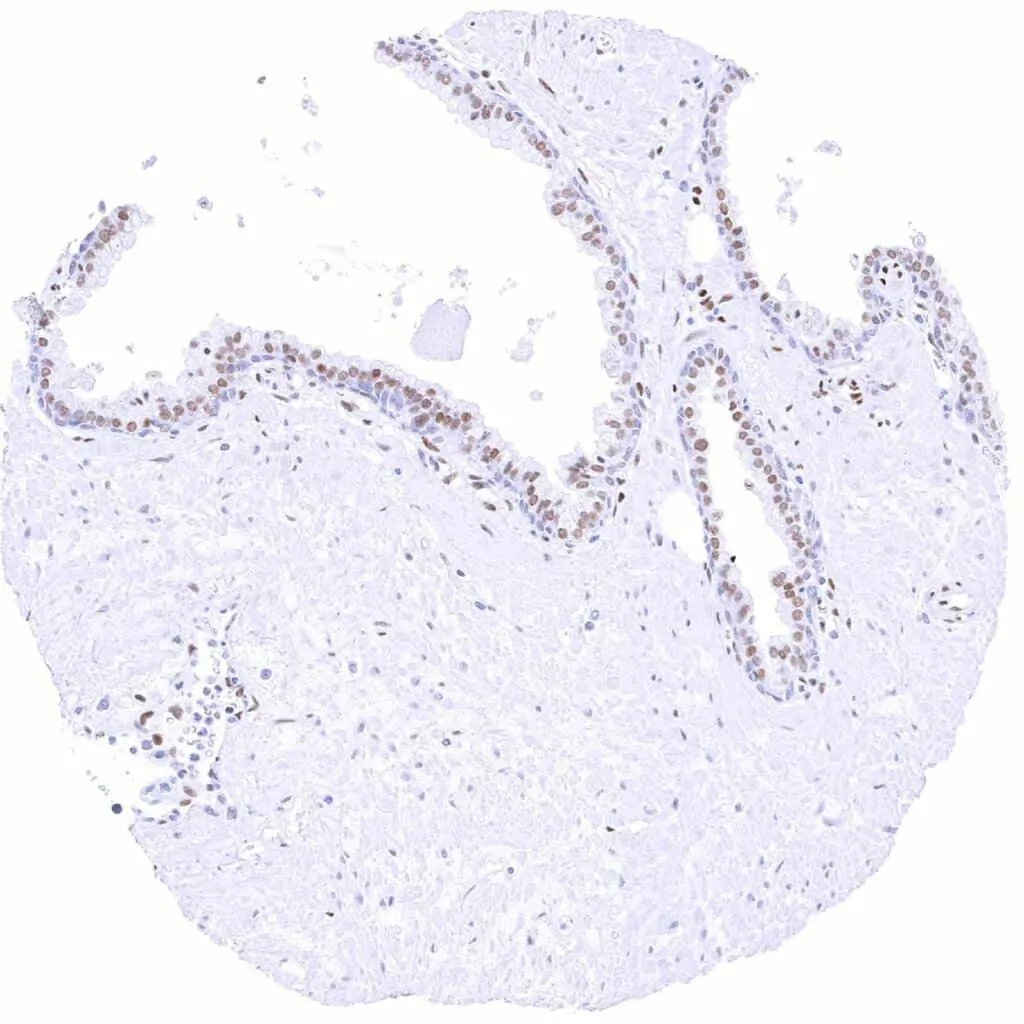

Prostate – Weak to moderate TLE1 staining in acinar cells. Staining is weak or absent in basal cells